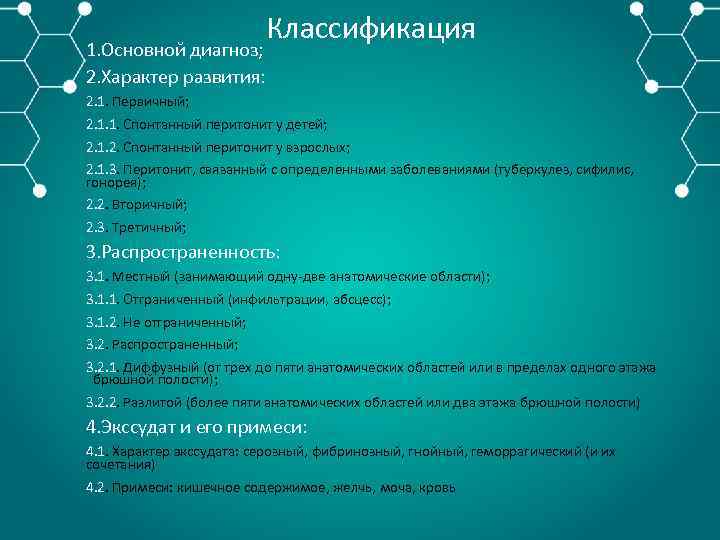

Перитонит – воспаление брюшины в результате интраабдоминального инфицирования. Первичный перитонит – развивается в результате гематогенного или лимфогенного инфицирования брюшной полости при отсутствии внутрибрюшного источника или транссудации специфической моноинфекции из других органов. Вторичный перитонит – наиболее частая и тяжелая форма абдоминальной инфекции, развивающейся в результате гнойно некротических заболеваний и повреждений полых и паренхиматозных органов живота и (или) осложнений в послеоперационном периоде (например, несостоятельность анастомоза). Третичный перитонит характеризуется персистирующим течением инфекционного процесса и развивается позже 48 ч. после успешного и адекватного хирургического лечения источника вторичного перитонита в результате контаминации брюшной полости полирезистентной нозокомиальной микробной флорой на фоне кишечной недостаточности

1. Основной диагноз; 2. Характер развития: Классификация 2. 1. Первичный; 2. 1. 1. Спонтанный перитонит у детей; 2. 1. 2. Спонтанный перитонит у взрослых; 2. 1. 3. Перитонит, связанный с определенными заболеваниями (туберкулез, сифилис, гонорея); 2. 2. Вторичный; 2. 3. Третичный; 3. Распространенность: 3. 1. Местный (занимающий одну две анатомические области); 3. 1. 1. Отграниченный (инфильтрации, абсцесс); 3. 1. 2. Не отграниченный; 3. 2. Распространенный; 3. 2. 1. Диффузный (от трех до пяти анатомических областей или в пределах одного этажа брюшной полости); 3. 2. 2. Разлитой (более пяти анатомических областей или два этажа брюшной полости) 4. Экссудат и его примеси: 4. 1. Характер экссудата: серозный, фибринозный, гнойный, геморрагический (и их сочетания) 4. 2. Примеси: кишечное содержимое, желчь, моча, кровь